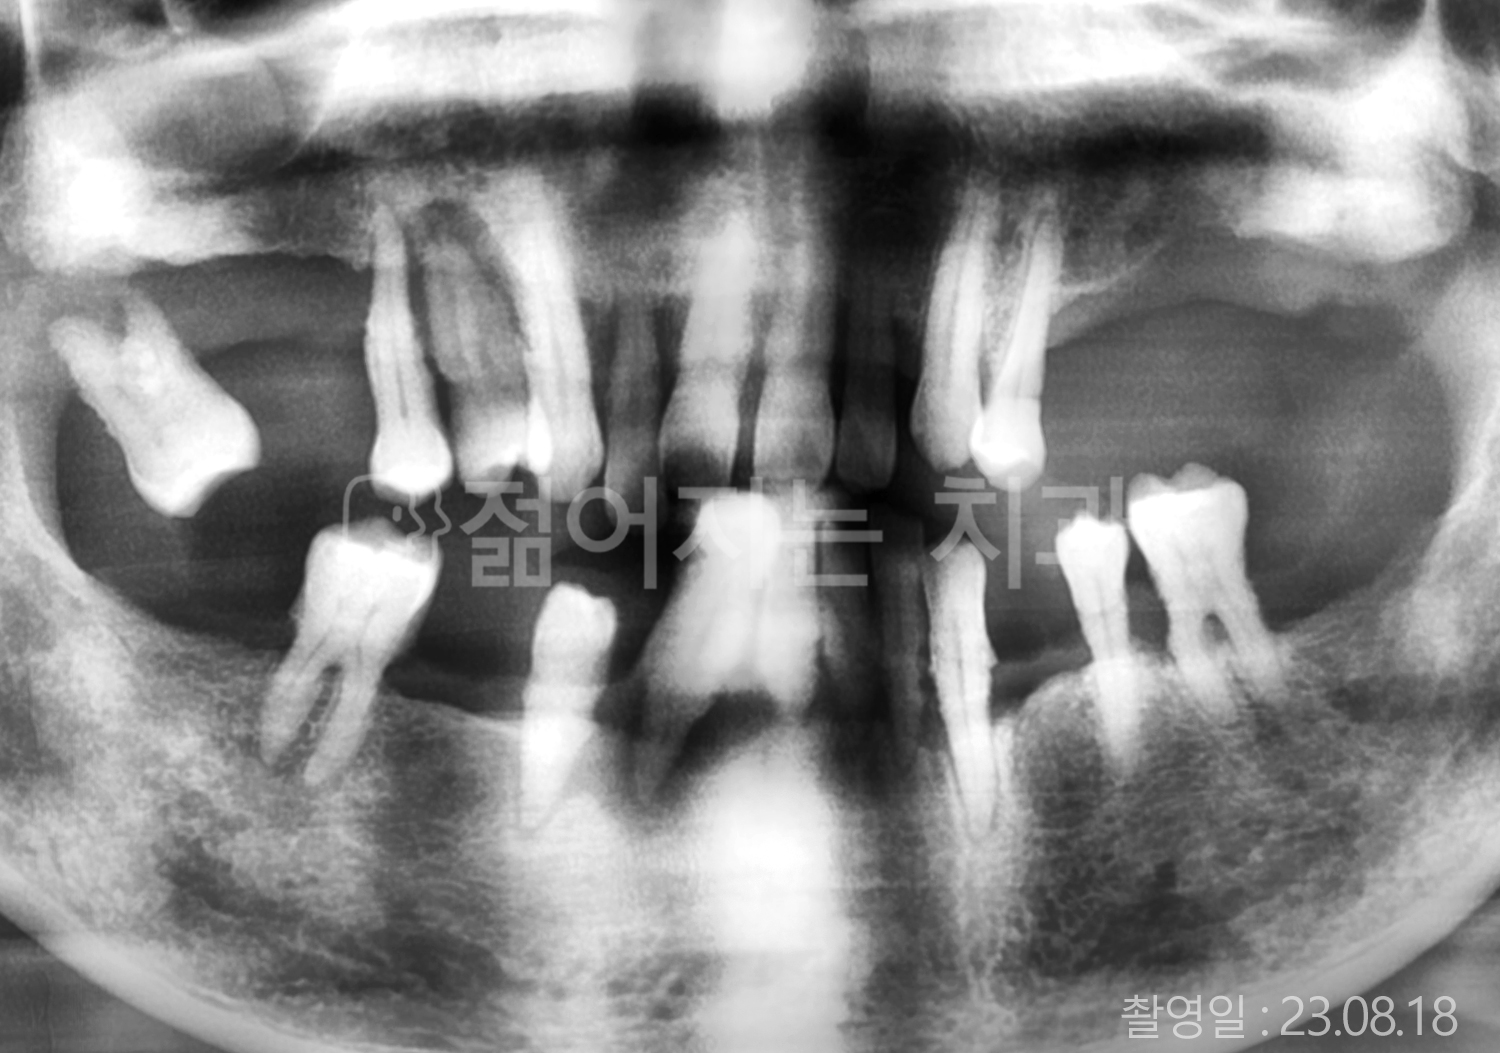

• 50대 전체치아 10개 이상 임플란트